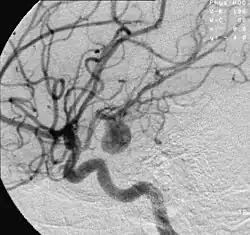

Angiografía de un aneurisma en una arteria cerebral.